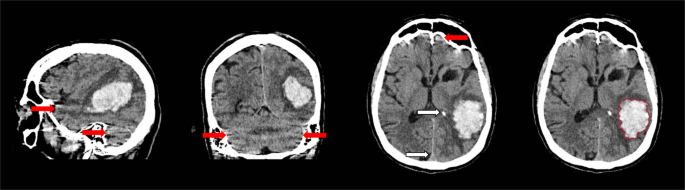

Computed Tomography (CT) imaging is the preferred modality for the initial assessment of patients presenting with symptoms of stroke in the majority of health care settings because it is readily available, can be performed fast and has high sensitivity for haemorrhage4. Generally, the appearance of haemorrhage on CT in the acute phase is distinct due to the hyperdensity of blood. However, segmentation of ICH can be challenging because of image noise, artefacts and cerebral parenchyma with similar appearance and density. Irregularity of the haematoma and different stages of clot formation may further contribute to obscure haemorrhage boundaries and internal heterogeneity. These difficulties are illustrated in Fig. 1.

Sagittal, coronal and axial view of intracerebral haemorrhage with internal heterogeneity and irregular boundaries. Linear high density regions are caused by streaking artefacts as a result of beam hardening (red arrows). Intracranial calcifications and structures such as the falx cerebri share similar density values (white arrows). Haemorrhage boundary manually defined by a trained observer (right).